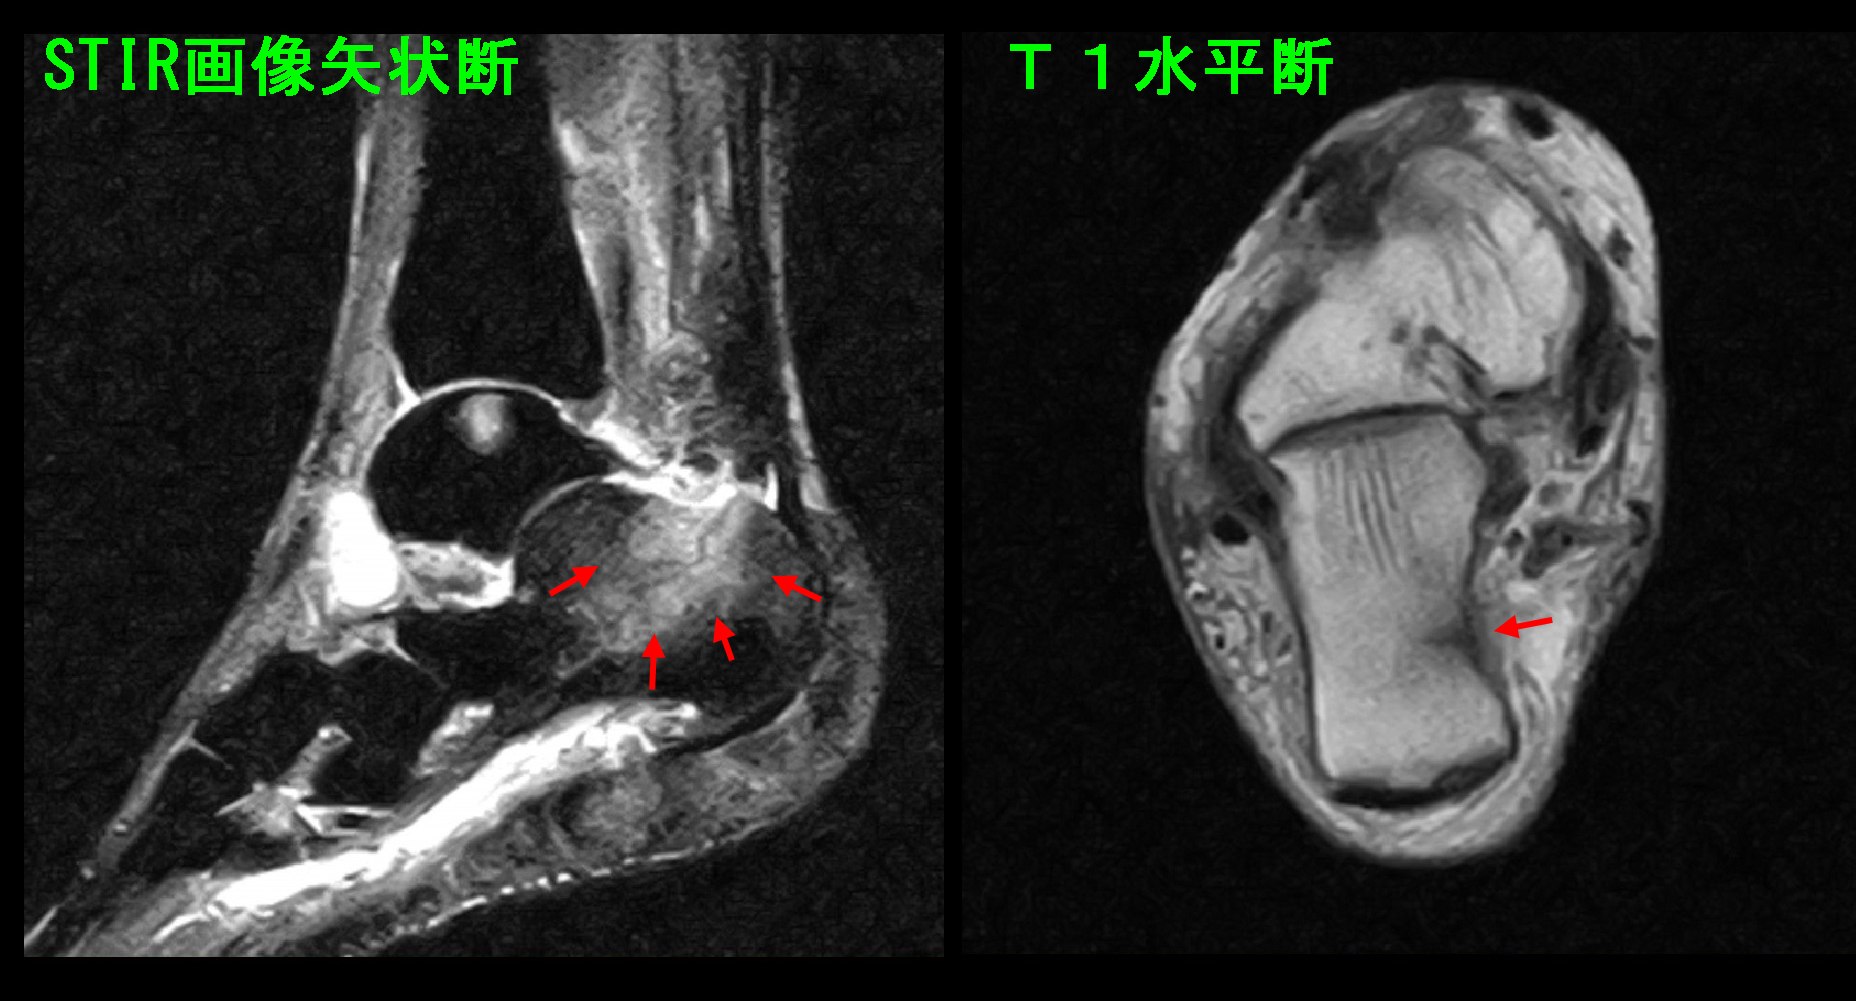

MRI検査を行うと、左側のSTIRの条件で黒い踵の骨(踵骨=しょうこつ)が白くなり、疲労骨折の状態でした。右側のT1という条件では内側の骨の壁が黒くなり、ひびと診断されました。

初診時MR画像.jpg